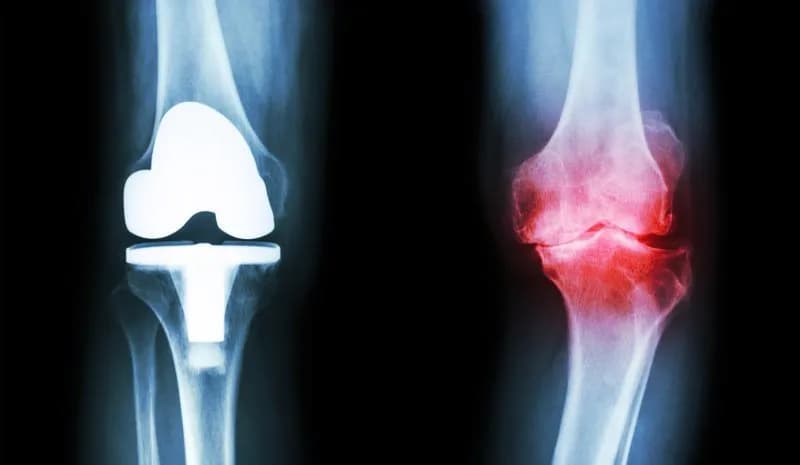

Dowiedz się, jaki lekarz leczy zwyrodnienia stawów i kiedy udać się do reumatologa lub ortopedy. Poznaj metody diagnostyki, skutecznego leczenia oraz sposoby na złagodzenie bólu stawów.